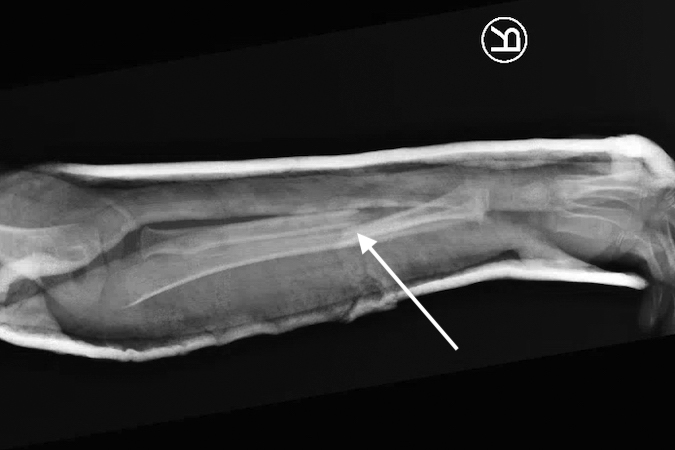

Greenstick fracture

- Pediatric forearm fractures are typically described as either complete or greenstick fractures.4

- Greenstick fractures are incomplete, partial thickness fractures in which only the cortex and periosteum are interrupted on one side of the bone but intact on the other side.4,18

- Greenstick fractures are more common among younger children under the age of 10 years, particularly boys, while completed or short oblique fractures are more common in older children.18,19

- The most common mechanism of injury is a fall on an outstretched hand (FOOSH), but other possible causes include car accidents, bike accidents, sports injuries, and non-accidental trauma.18

- Radiology studies - X-ray